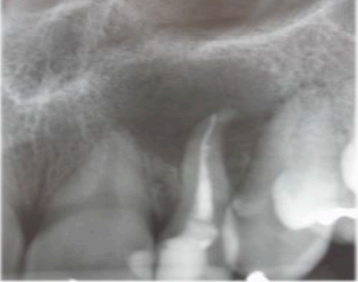

A cirurgia para endodôntica é um procedimento que tem como finalidade resolver problemas que não puderam ser solucionados pelo tratamento endodôntico convencional, ou quando este não é possível.

Responda à questão relacionada ao caso clínico a seguir: A paciente A.G.T., 28 anos, sexo feminino, relata história de secreções frequentes e sintomatologia dolorosa à palpação na região do dente 22. Compareceu à clínica cirúrgica com um encaminhamento da endodontia, solicitando avaliação e conduta em relação ao dente 22. Após exame clínico da paciente e avaliação do exame de imagem do dente 22, (que está reproduzido na figura a seguir), ficou evidente a necessidade de tratamento cirúrgico para resolução do quadro clínico apresentado.

Fonte: O autor, 2024.

Em relação ao quadro clínico e a imagem radiográfica acima, analise os itens a seguir.

I- Realizar a extração desse dente.

II- Realizar apenas a punção aspirativa na área da lesão.

III- Realizar curetagem da lesão e apicectomia.

IV- Realizar curetagem da lesão.

V- Realizar curetagem da lesão e enxerto ósseo.

Está CORRETO apenas o item